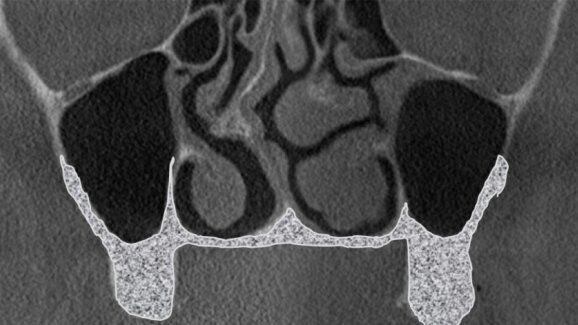

Klasyfikację oparto na obrazie z tomografii, jaki uzyskuje się w przekrojach czołowych (wieńcowych) lub prostopadłych do krzywej panoramicznej ułożonej równolegle do łuku zębowego górnego. Klasa „zero” (Tab. 1) została wyróżniona jako sytuacja kliniczna, w której brak bezwzględnych wskazań do zabiegu podniesienia dna zatoki szczękowej z 2 powodów:

Kolejne klasy wyróżnia się na podstawie grubości kostnej ściany przedsionkowej zatoki lub podniebiennej. Jeżeli ściana przedsionkowa jest cieńsza niż podniebienna, wówczas w domyśle łatwiejszy dostęp jest od przedsionka, więc przypadek klasyfikuje się do klasy pierwszej.

Występują jednak sytuacje, kiedy to w badaniu CBCT zauważamy jednakowej grubości ścianę przedsionkową oraz podniebienną. Jest to sytuacja, w której przypadek przyporządkowujemy do klasy drugiej.

W chwili, gdy ściana podniebienna jest cieńsza niż policzkowa, występuje klasa trzecia. U tego samego pacjenta może wystąpić anatomicznie klasa pierwsza po stronie prawej i klasa druga po stronie lewej. Różnice te związane są z takimi czynnikami, jak: